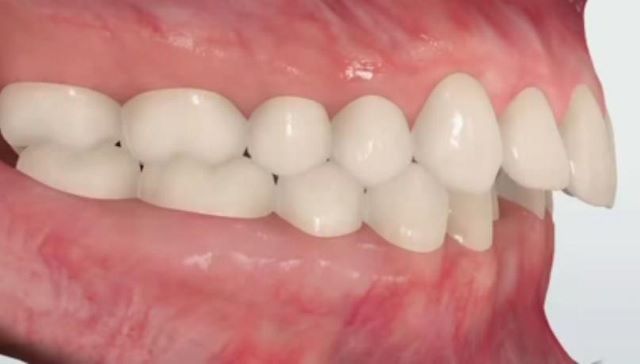

מנשך תקין

מנשך שבו השיניים בלסת העליונה ובלסת התחתונה,נפגשות האחת מול השנייה(ראה תמונות מצורפות).